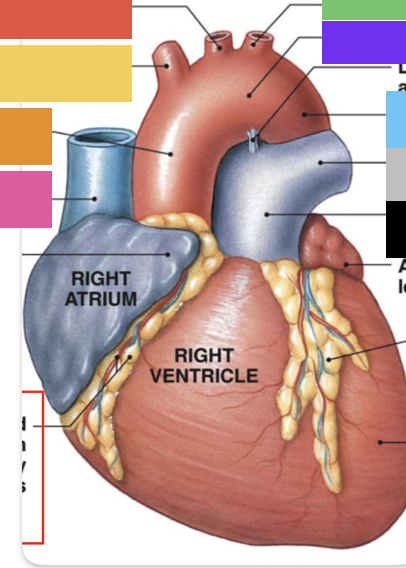

right atrium

right auricle

right ventricle

superior vena cava

inferior vena cava

pulmonary trunk